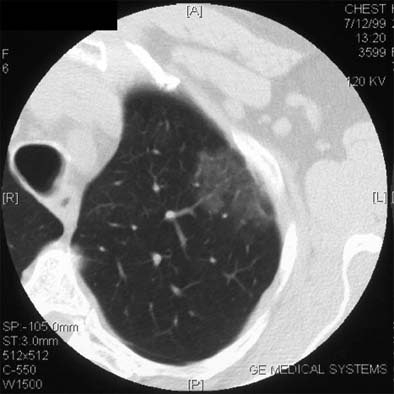

| Non-solid nodule. |

| Non-solid nodule at baseline (left) and follow-up (right). |